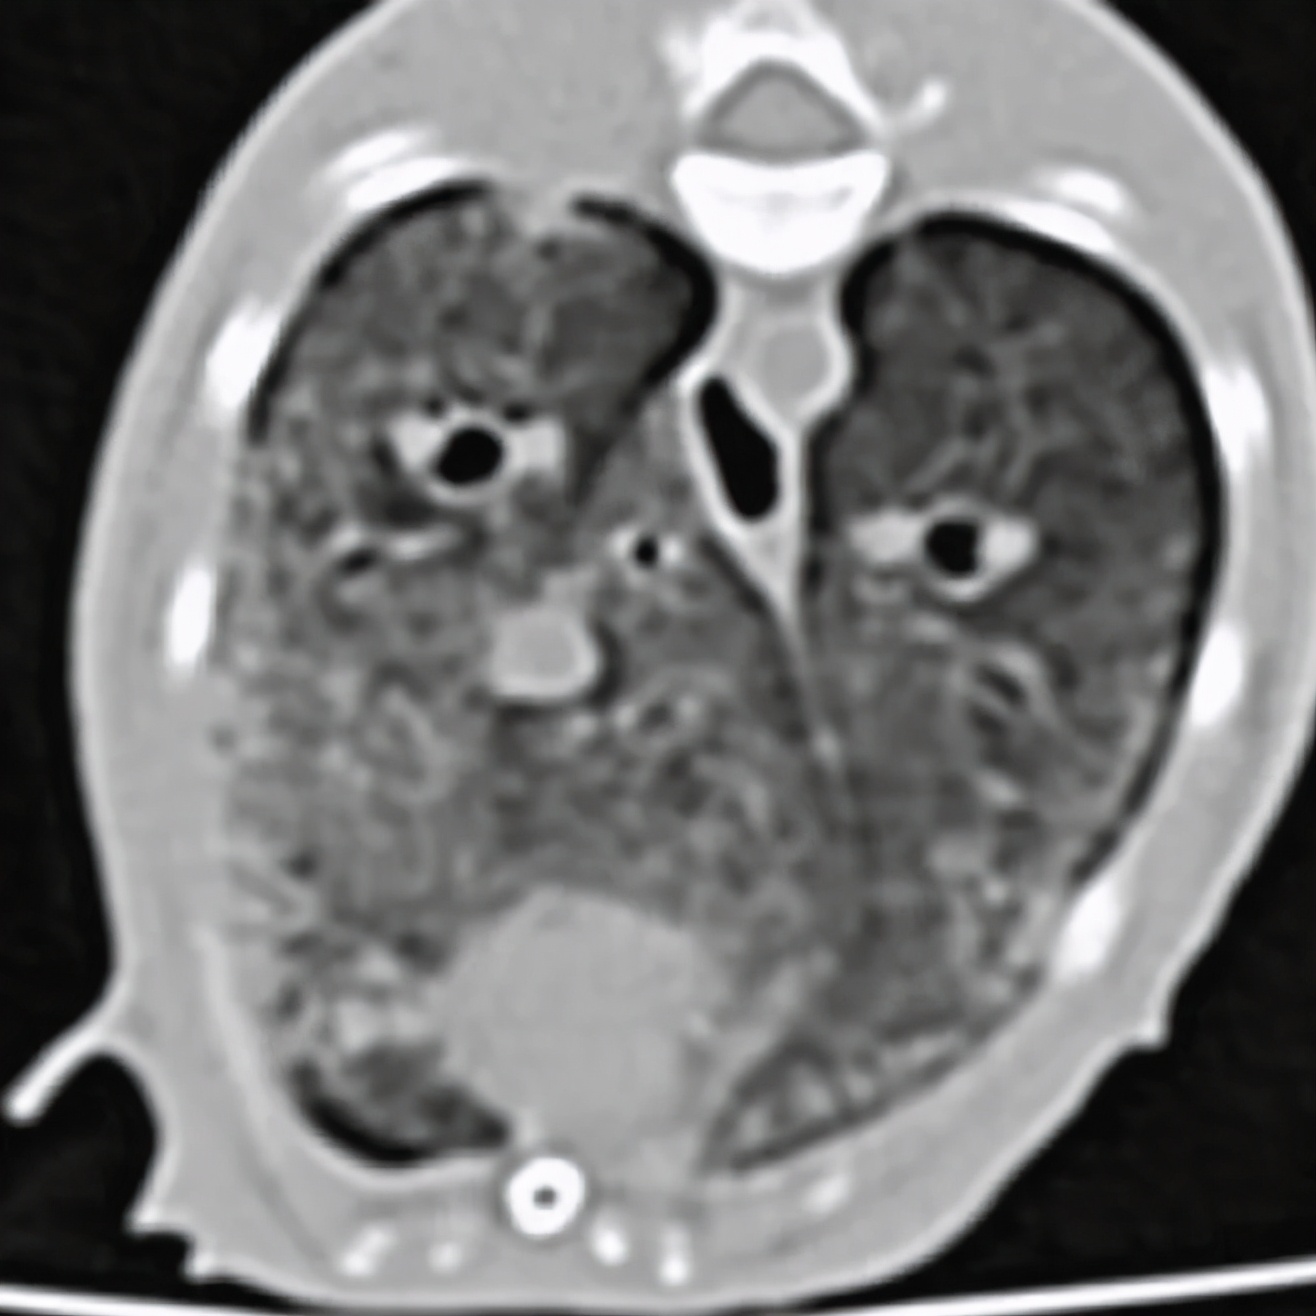

4个月大的家养短毛猫,咳嗽、干呕。

疱疹病毒等检测隐形,抗生素治疗不敏感,血液检查发现高钙血症,CT显示主动脉弓、主动脉根部矿化,肺部表现与矿化、纤维化或炎症表现一致。

经详细病史排查及第三方机构检测,发现主人饲喂的罐装零食存在维生素过量,诊断为高维生素D中毒。